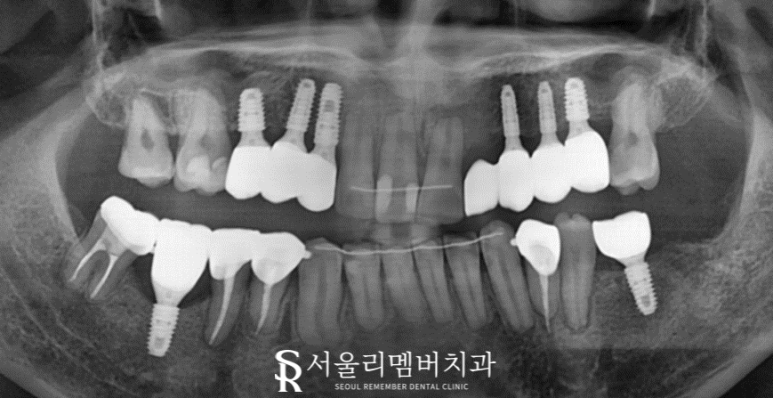

약 2년에 가까운 시간이 흐른 뒤, 남성역 치과 의 모든 치료가 마무리되었습니다.

처음에는 충치 때문에 검게 변색되어 있던 것들이 깨끗하게 변했으며 들쑥날쑥 배열에서 고른 이로 변화된 모습이네요.

잇몸은 선천적인 영향도 있고 이미 악화된 상황이라 개선하는 데에 한계가 있었습니다.

그래도 남은 문제들은 별 이상 없이 해결된 것 같네요.

이제 편하게 식사하실 일만 남았습니다~

앞으로는 청결한 구강관리를 통해 오래오래 보철을 사용하기 바랍니다^^

오늘은 임플란트를 동반한 교정 케이스를 소개해 드렸는데요.

통합 치의학과 전문의의 진료로 두 가지 치료를 한 번에 받을 수 있었네요.